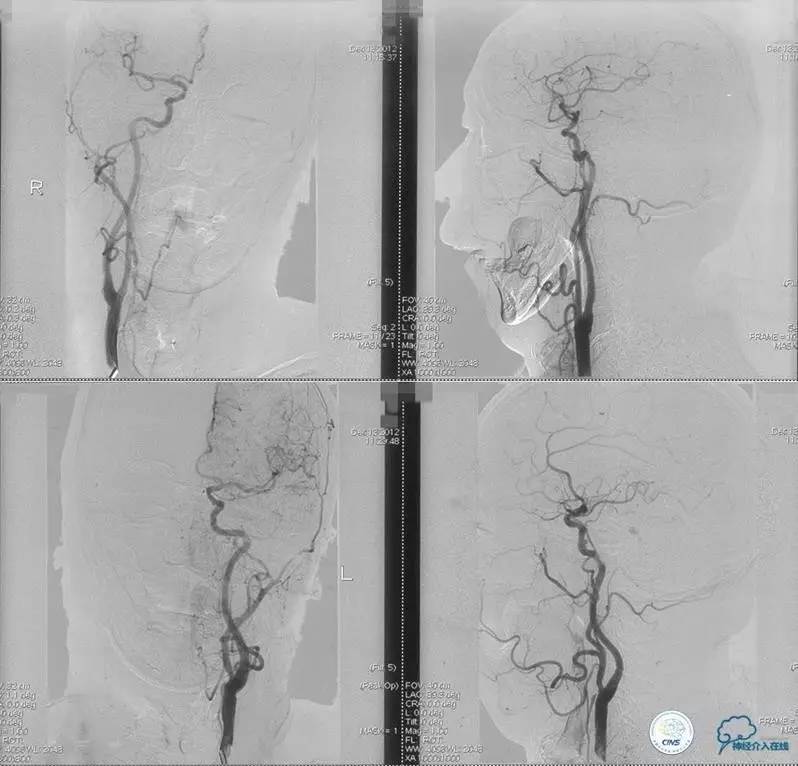

术前DSA

▼2013-12-13

▼2013-12-27

术后仍残余部分狭窄,但头晕明显缓解。

术后3个月复查时予行支架内球囊扩张,狭窄改善。